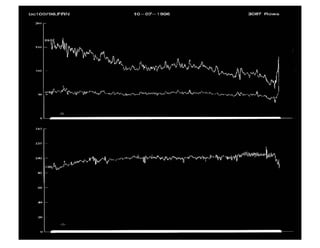

Prueba de la Tabla de Inclinación Negativa : En este caso la presión arterial normal (trazados superiores) y la Frecuencia Cardiaca (trazado inferior) se mantiene durante u  periodo de 40 minutos de inclinación.

Tilt Test  en un paciente con  Síncope Neurocardiogénico Vasodepresor .  En este caso la presión arterial (registro superior) se reduce notablemente desde  150/70 mm Hg a 50/30 mm Hg a  los 25 minutos, pero la FC (trazado inferior ) no disminuye. En ese momento, el paciente desarrolla sintomas tipicos

Cambios característicos inducidos por el tilt Test en un paciente con Síncope Cardioinhibitorio NeuroCardiogénico.  A los 15 minutos de la prueba se advierte el descenso dramático de la PA (trazado superior) desde 150/60 mm Hg a 50/20 mm Hg en un periodo de 1 minuto, mientras que la FC (trazado inferior) disminuyó desde 65 latidos/min a 30 latidos/ min. Entonces el paciente desarrolló los sintomas típicos. Al remover la inclinación se produjo una rápida recuperación.

Prueba de laTabla de Inclinación Negativa : En este caso la presión arterial normal (trazados superiores) y la Frecuencia Cardiaca (trazado inferior) se mantiene durante u periodo de 40 minutos de inclinación.

Cambios característicos inducidospor el tilt Test en un paciente con Síncope Cardioinhibitorio NeuroCardiogénico. A los 15 minutos de la prueba se advierte el descenso dramático de la PA (trazado superior) desde 150/60 mm Hg a 50/20 mm Hg en un periodo de 1 minuto, mientras que la FC (trazado inferior) disminuyó desde 65 latidos/min a 30 latidos/ min. Entonces el paciente desarrolló los sintomas típicos. Al remover la inclinación se produjo una rápida recuperación.

Hipotensión Ortostática. Paciente con historia de desmayos. Desde el comienzo del tilt test la PA disminuyó de 156/54 mm Hg a 60/40 mm Hg en 30 minutos, asociado con un aumento de la FC desde 85 latidos/minuto a 100 latidos/minuto. A los 30 minutos del tilt test se sintió mareado.